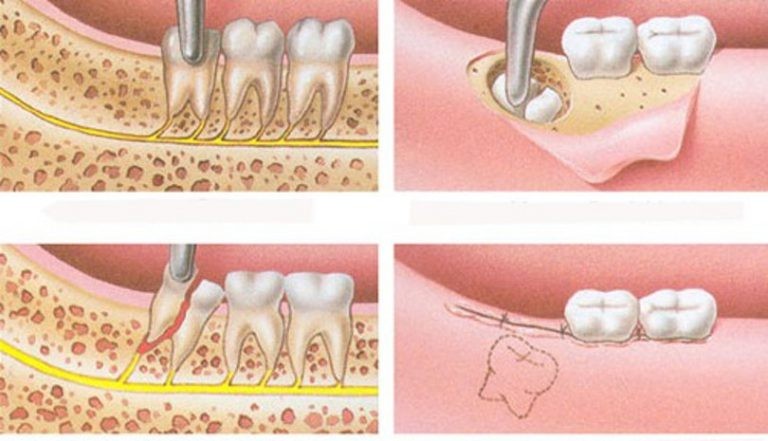

3. Tiểu phẫu cắt bỏ lợi

Nếu lợi trùm răng gây đau nhức hoặc tái phát thường xuyên thì phải tiến hành phẫu thuật cắt bỏ.

Cắt lợi trùm là một tiểu phẫu nhỏ được sử dụng trong nha khoa giúp loại bỏ phần lợi mọc trùm lên răng khôn. Trong trường hợp răng khôn mọc thẳng, các nha sĩ sẽ tiến hành thủ thuật này. Cắt lợi trùm sẽ giúp giải phóng không gian và tạo điều kiện cho răng khôn tiếp tục mọc lên.

Khi thực hiện cắt lợi trùm, các nha sĩ sẽ tiến hành vệ sinh khoang miệng và gây tê phần lợi cần loại bỏ. Sau đó, nha sĩ sẽ sử dụng Laser để cắt mặt trong, mặt ngoài và loại bỏ phần gốc lợi trùm. Cảm giác đau, sưng và rỉ máu nhẹ sẽ là điều không thể tránh khỏi sau khi cắt lợi trùm. Thông thường, sau khoảng 1-2 tuần phần lợi sẽ hoàn toàn bình phục.

4. Nhổ răng

Trong trường hợp phần lợi bị viêm và sưng nhẹ cho răng khôn mọc. Đồng thời, phần lợi viêm không bị nhiễm trùng, phần lợi viêm sẽ hoàn toàn có thể tự khỏi sau 3-4 ngày. Tuy nhiên, một điều chắc chắn, phần lợi trùm này sẽ tiếp tục bị sưng và viêm trở lại trong tương lai. Lý do là bởi, răng khôn sẽ tiếp tục phát triển. Khi phần lợi bị hở ra một phần trên bề mặt răng khôn, đây sẽ trở thành nơi dễ bị kẹt lại thức ăn. Từ đó, vi khuẩn sẽ lại gây viêm cho phần lợi này.

Do vậy nếu răng khôn vẫn không thể mọc vào vị trí bình thường thì cần phải phẫu thuật để lấy nó ra. Thông thường, nha sĩ sẽ khuyên người bệnh nhổ răng khôn cả hàm trên và hàm dưới để ngăn răng trên bị cắn vào nướu và khiến việc nhiễm trùng tái phát.

viêm lợi trùm

Nhổ răng là sẽ giúp giải quyết tình trạng viêm